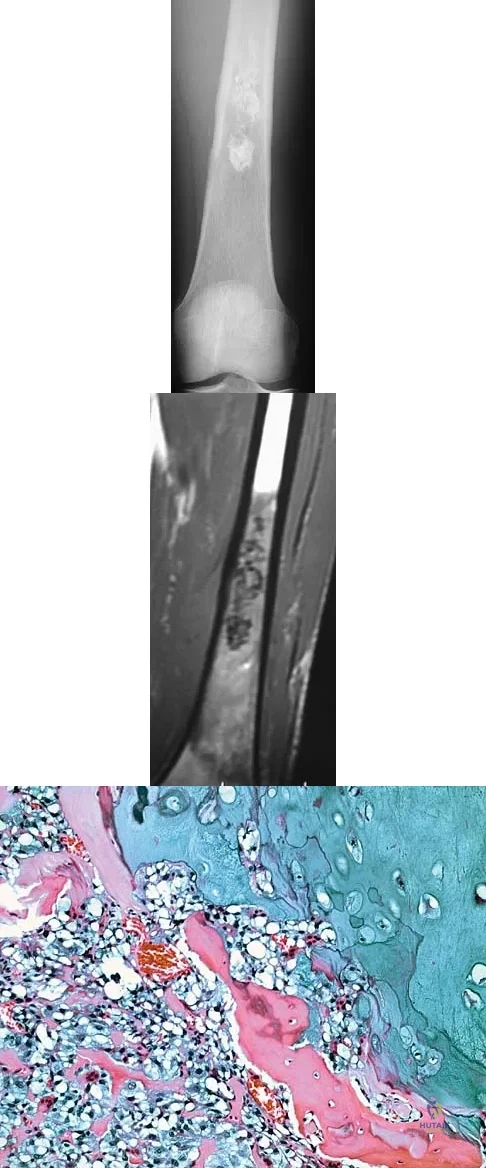

Question 4

Following preoperative chemotherapy, the percent of tumor necrosis has been shown to be of prognostic value for which of the following tumors?

Question 8

A 77-year-old man has had increasing right knee pain for the past 3 months. A radiograph and coronal T1-weighted MRI scan are shown in Figures 19a and 19b. A biopsy specimen is shown in Figure 19c. What is the most likely diagnosis?

Explanation